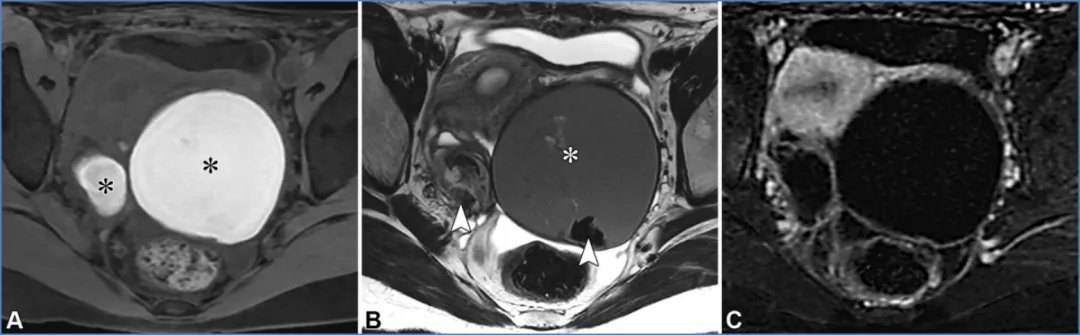

对于卵巢来源的病变,子宫内膜异位囊肿和出血性囊肿是可能的诊断。子宫内膜异位囊肿是子宫内膜异位症的常见表现,子宫内膜异位症影响10%的育龄女性,并与慢性疼痛和不孕相关(10)。子宫内膜异位症的特征是子宫内膜腺体和间质出现在子宫内膜外,导致炎症、纤维化和结构扭曲。影像学检查可能会发现子宫内膜异位囊肿和深部子宫内膜异位症。子宫内膜异位囊肿表现为卵巢囊肿,通常为多灶性和双侧性,由于周期性出血,在T1加权像上呈弥漫性显著高信号,在T2加权像上呈阴影(变暗)改变(图21)。由纤维化和含铁血黄素形成的厚T2低信号 rim、由血块形成的T2低信号斑点以及病变长期存在,均会提高子宫内膜异位囊肿诊断的特异性(65,66)。

图21. 一位20岁痛经女性患者的双侧子宫内膜异位囊肿。(A、B)轴位脂肪抑制T1加权像(A)和T2加权像(B)显示了子宫内膜异位囊肿的典型特征,如双侧T1高信号病灶(A中的*)伴T2信号衰减(B中的*)、T2低信号囊壁以及病灶内T2低信号斑点(B中的箭头),所有这些均提示慢性反复出血。(C)对比增强脂肪抑制T1加权减影图像证实无强化的实性组织。